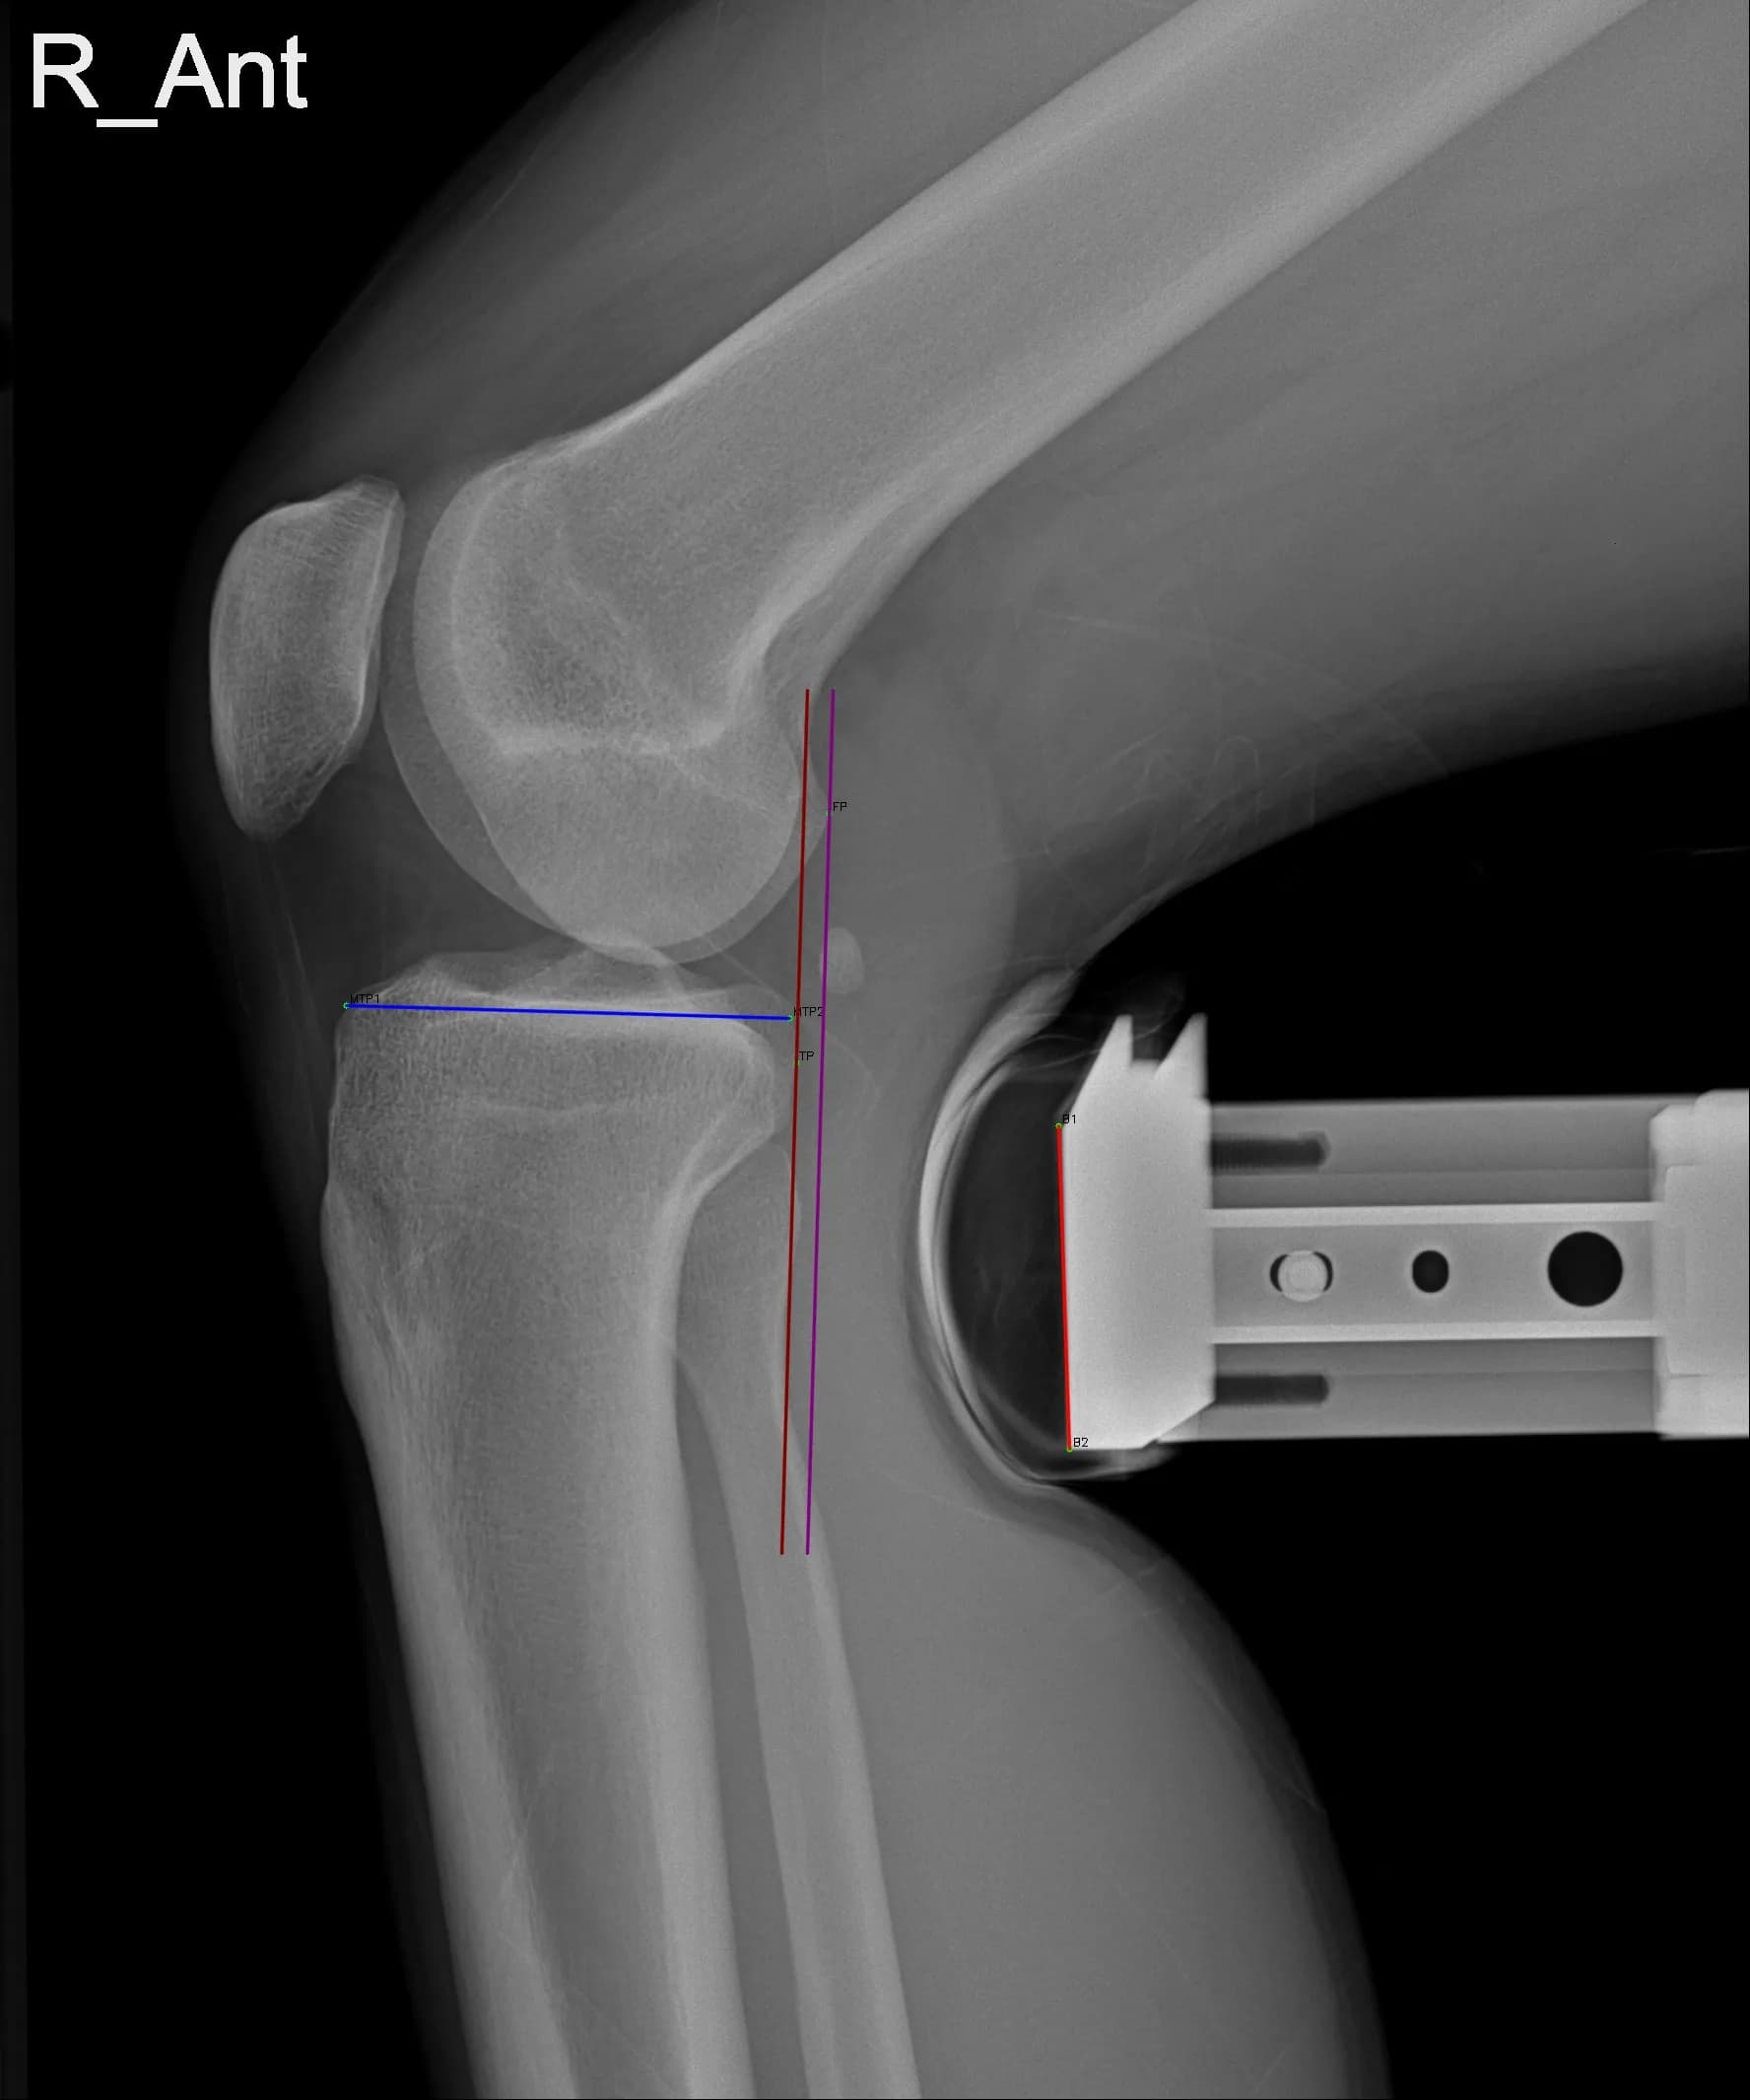

Musculoskeletal X-ray AI Analysis

부위를 클릭하여 결과 이미지를 확인하실 수 있습니다.